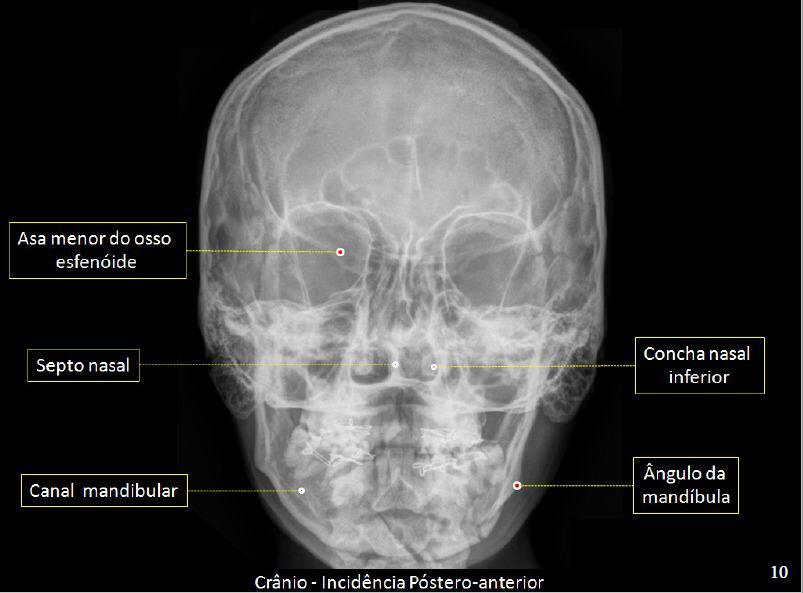

sa menor do osso esfenóide Concha nasal Septo nasal inferior Ângulo da Canal mandibular mandíbula Crânio - Incidência Póstero-anterior